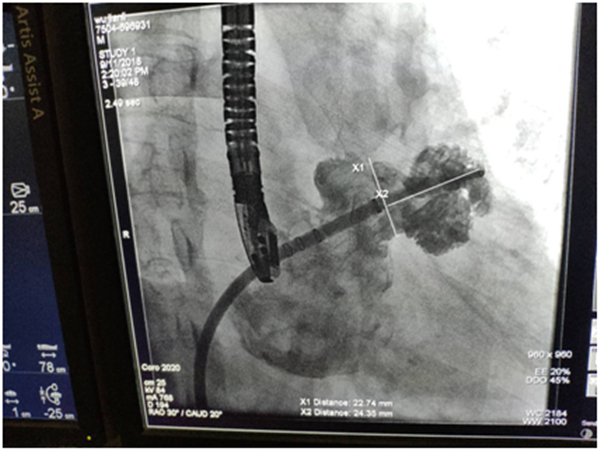

术中TEE测量心耳大小00 18mm×30mm,450 20mm×33mm, 90018mm×30mm, 135017mm×18mm,DSA测量心耳开口22mm,深度27mm。 根据TEE及DSA测量的结果,综合考虑后,选用27mm WATCHMAN左心耳封堵器,伞器展开后,测量计算压缩比为19%-25%,牵拉稳定,满足PASS原则,释放器械,成功封堵。